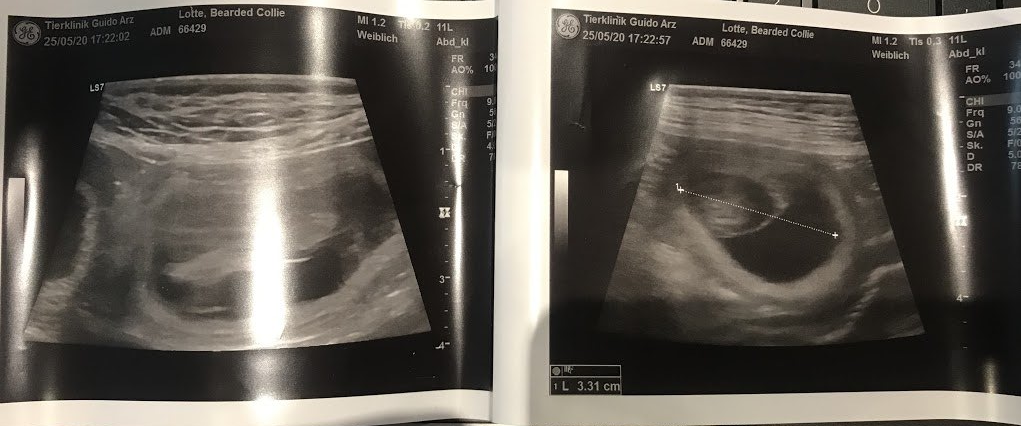

L'échographie l'a confirmé... Lotte attend des bébés et nous sommes à nouveau ravis.